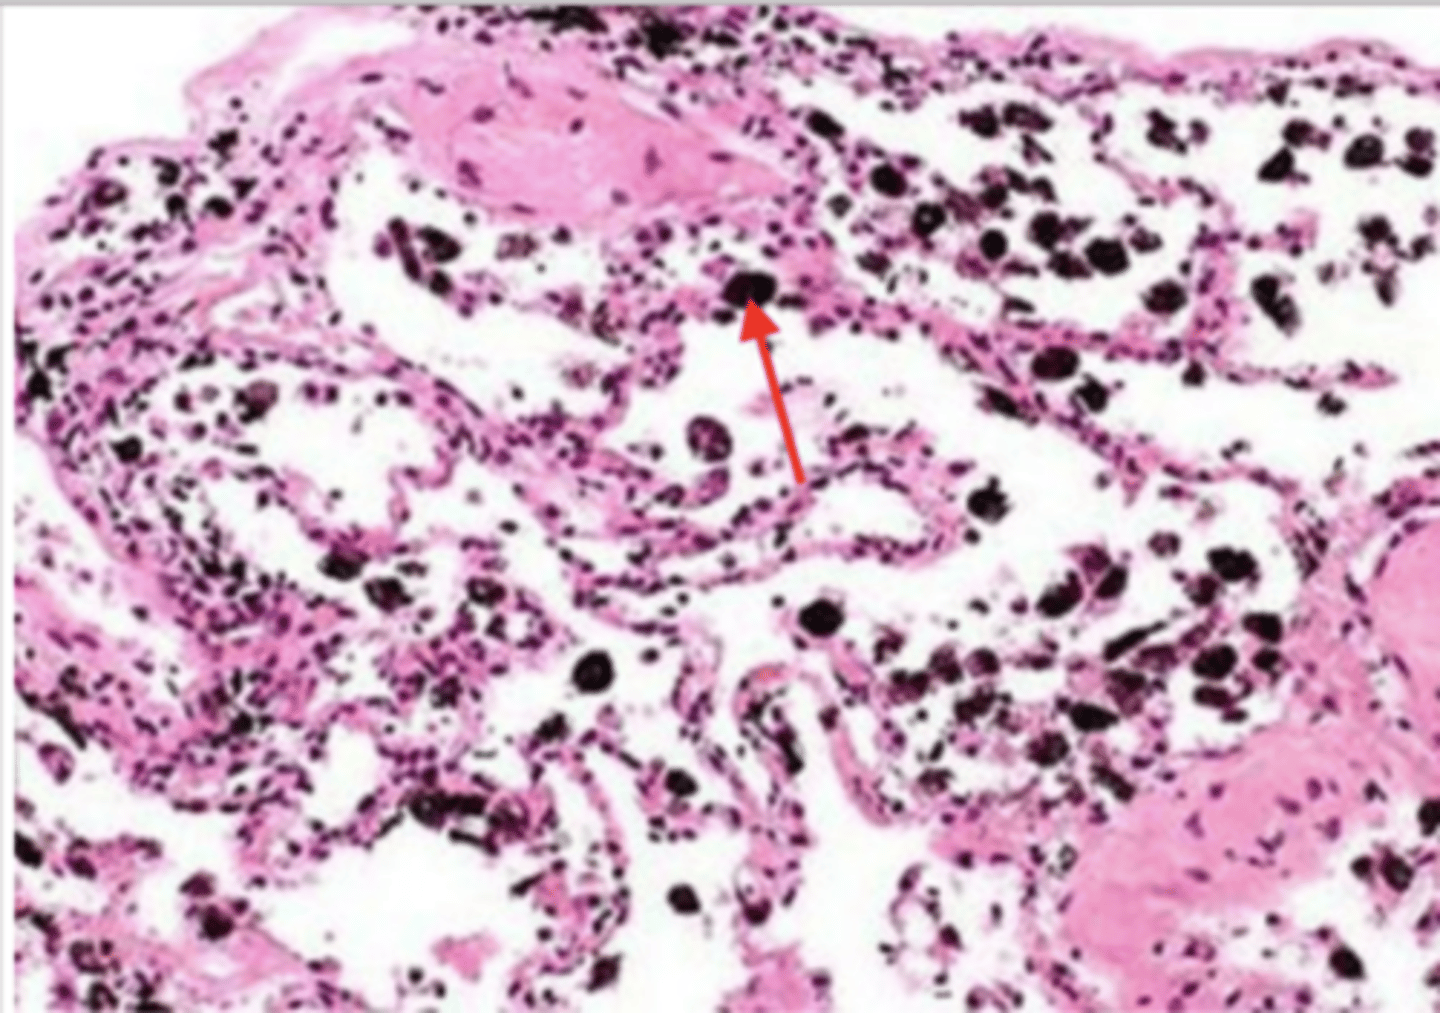

smoker's lung

alveolus (of smoker's lung)

carbon deposits (tar)